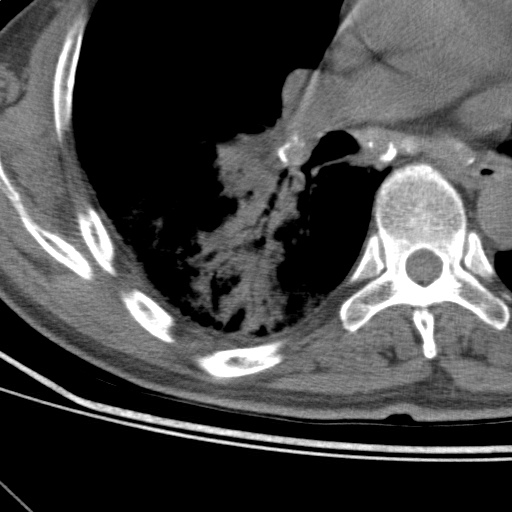

以下是引用随光逐影在2009-5-1 13:53:00的发言:[br]考虑为:1)两肺血行播散型肺结核;2)右肺下叶炎症感染。3)右侧胸膜增厚。